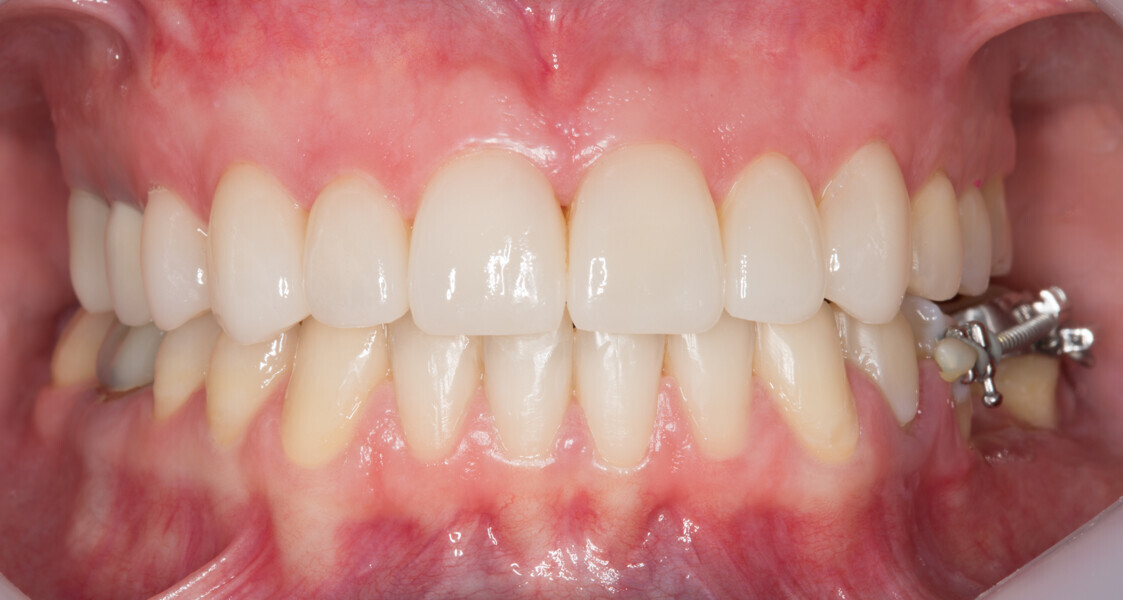

Fig. 25: Final results of the analogue and digital approach.

Fig. 26: Final results of the analogue and digital approach.

Fig. 27: Final results of the analogue and digital approach.

Fig. 28: Final results of the analogue and digital approach.

Fig. 29: Final results of the analogue and digital approach.

Fig. 30: Final results of the analogue and digital approach.

Fig. 31: Final results of the analogue and digital approach.